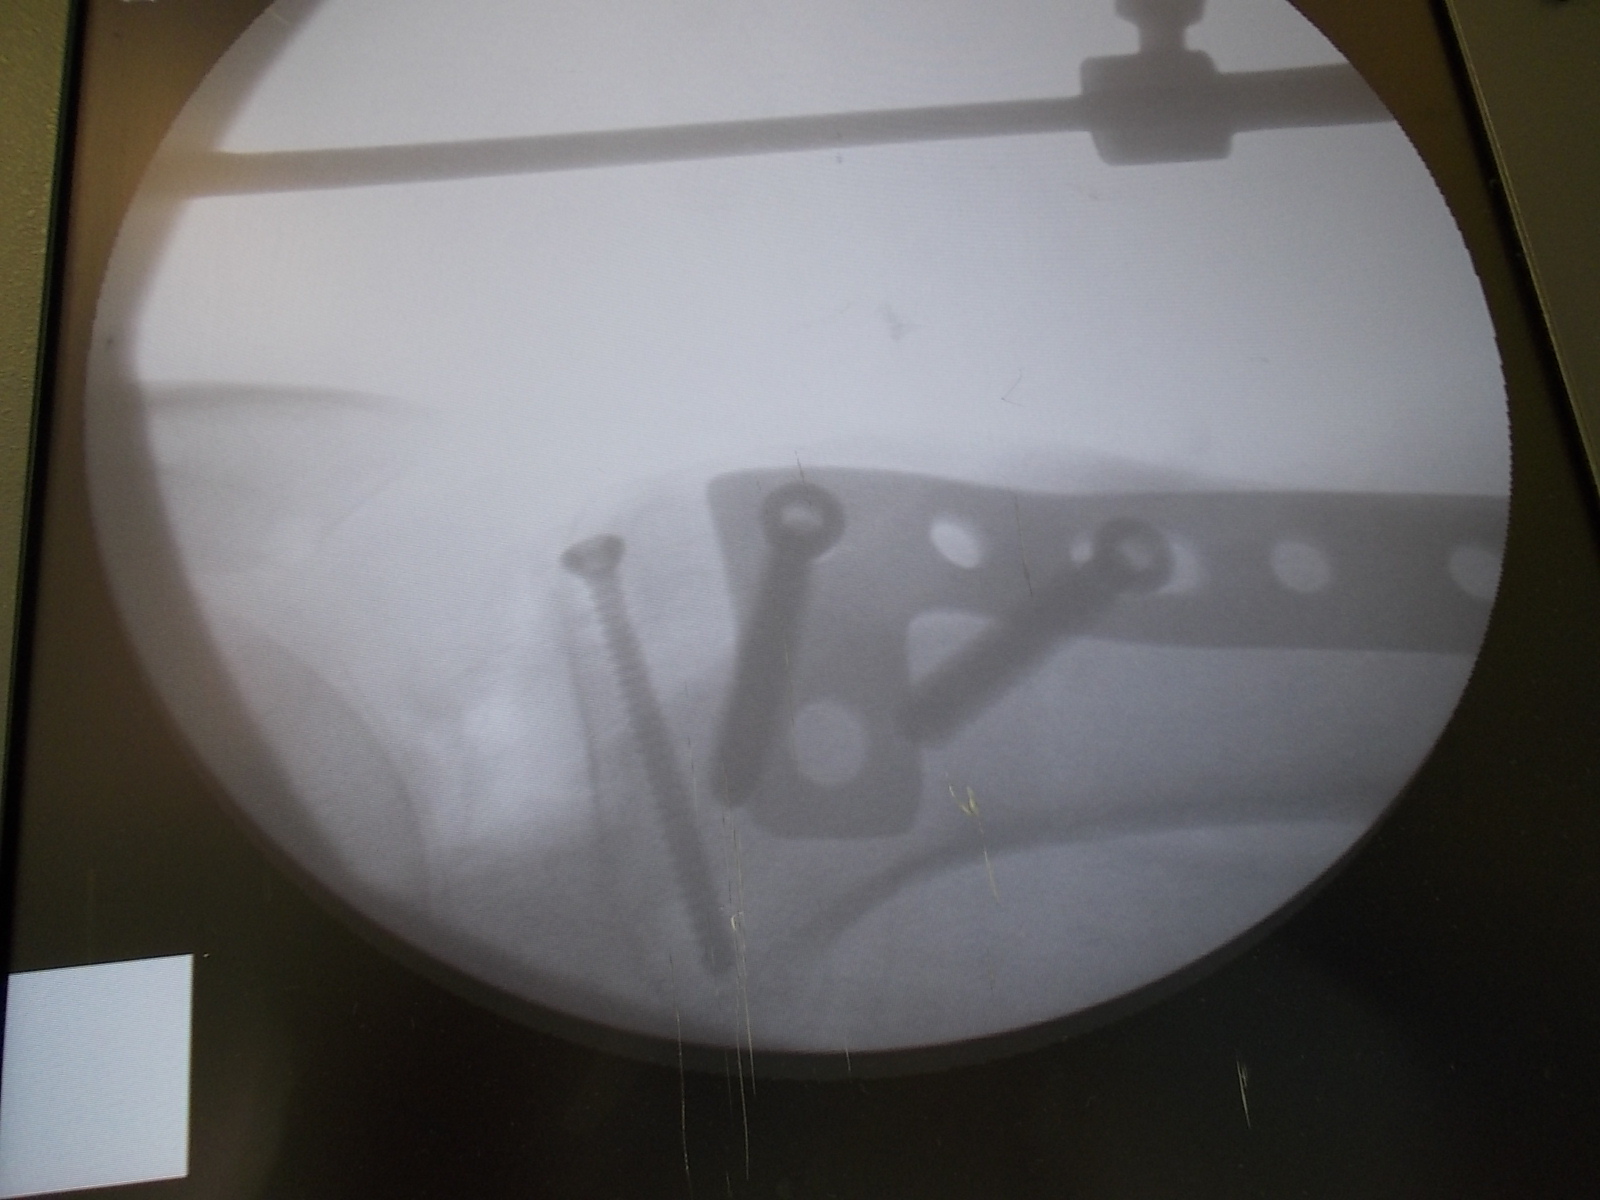

Операция - открытая репозиция, остеосинтез большеберцовой кости опорной пластиной с костной ксенопластикой маетриалом "Остеоматрикс". На контрольных снимках в три и шесть месяцев имеется консолидация перелома, миграции фиксатора нет, имеется остеоинтеграция ксенопластического материала. Функция коленного сустава полная.